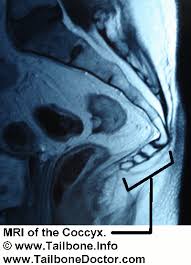

Coccyx Pain Cancer

Coccyx Pain Cancer.